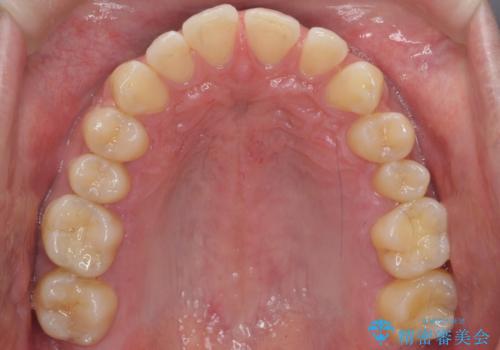

患者様の歯は咬耗といって削れて短くなっていたため、セラミックでかぶせると隙間をうめるため横長の歯になりそうでした。術後の見た目は矯正の方が自然にみえるとお伝えしました。

時間はかかるが矯正治療で天然の歯の隙間をつめて歯を削らなくて済むというご案内をしたところ、セラミックでかぶせるのはやめて、矯正治療を行うことになりました。

インビザライン(マウスピース矯正)は小さな隙間を閉じるのは得意です。

ただし、上に隙間が余っている状態ですと、ただ閉じようとしても上の前歯が中に入らないと隙間が閉じないため、下の歯の位置によっては隙間が閉じ切れなくなります。

その場合は下の歯を上の前歯から離す方向に圧下したりする動きが必要になり、全体矯正が必要になります。